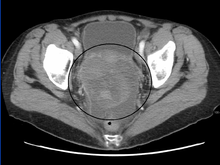

CT scanning is preferred to assess the extent of the tumor in the abdominopelvic cavity, though magnetic resonance imaging can also be used.[13] CT scanning can also be useful for finding omental caking or differentiating fluid from solid tumor in the abdomen, especially in low malignant potential tumors. However, it may not detect smaller tumors. Sometimes, a chest x-ray is used to detect metastases in the chest or pleural effusion. Another test for metastatic disease, though it is infrequently used, is a barium enema, which can show if the rectosigmoid colon is involved in the disease. Positron emission tomography, bone scans, and paracentesis are of limited use; in fact, paracentesis can cause metastases to form at the needle insertion site and may not provide useful results.[18] However, paracentesis can be used in cases where there is no pelvic mass and ascites is still present.[18] A physician suspecting ovarian cancer may also perform mammography or an endometrial biopsy (in the case of abnormal bleeding) to assess the possibility of breast malignancies and endometrial malignancy, respectively. Vaginal ultrasonography is often the first-line imaging study performed when an adnexal mass is found. Several characteristics of an adnexal mass indicate ovarian malignancy; they usually are solid, irregular, multilocular, and/or large; and they typically have papillary features, central vessels, and/or irregular internal septations.[16] However, SCST has no definitive characteristics on radiographic study.[20]